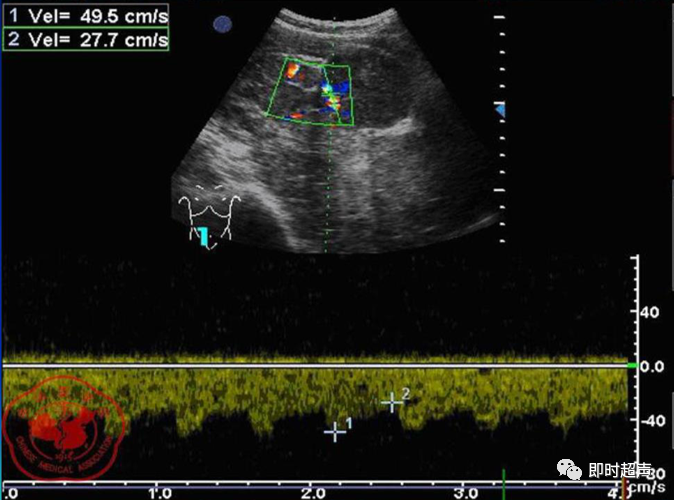

• GIST的发病机制与KIT信号通路的激活有关。• KIT是一种酪胺酸激酶跨膜受体蛋白,未经“装配”过的KIT蛋白是一种非活化的单体,参与细胞膜形成。几乎所有GIST都表达了KIT蛋白,而且大多突变的KIT基因保留了表达KIT蛋白的特性。c-kit内的突变主要见于恶性病例,特别是外显子11的点突变,还有外显子9、13和17,可以导致本质的或配体独立的c-kit激活,引发细胞的无序增殖和凋亡。这些具有功能的突变是GIST发病机理的关键,并且与肿瘤的恶性程度和预后较差相关。• GIST约75%发生于50岁以上老年人,中位年龄为58岁,无明显差异。• 可以发生在消化道从食道到肛门的任何部位,偶尔可原发于网膜、肠系膜和腹膜后,约50%发生在胃,25%发生在小肠,不足10%发生于食管、结肠及直肠。大体观察:肿块多境界清楚,类圆形,结节状,部分有假包膜。切面灰白、灰红,质韧,部分质嫩呈鱼肉状,伴有出血、坏死、囊性变。• 肿瘤组织主要由两种细胞组成,一种为长梭形细胞,细胞质丰富,嗜酸性,细胞核呈梭形或杆状;另一种为上皮样圆形或多角形细胞,细胞肥胖,胞质少。两种瘤细胞常呈束状、编织状或旋涡状排列。• 部分病例细胞异型明显,核分裂象增多,可见病理性核分裂象和瘤巨细胞。梭形细胞界不清楚,胞质丰富,淡染,轻度嗜伊红或略嗜碱,可有纤细、长梭形、短梭形或胖梭形、卵圆形,可见核仁。细胞核两端钝圆,部分病例胞质呈空泡状,位于核一端形成核端空泡胞,多呈交叉束状、旋涡状、席纹状及栅栏状排列。上皮样细胞胞浆丰富或透亮,多呈弥漫片状、束状或巢状排列。肿瘤间质可有出血、囊性变、坏死及黏液变,可见炎性细胞浸润。CD34抗原是一种115kd的糖基化蛋白,50%~80% GIST的CD34表达为阳性,CD34对鉴别GIST和典型的平滑肌瘤,神经鞘瘤还是非常有用的标记物,因后两者的CD34一般是阴性的。但CD34在诊断GIST上其特异性受到限制,一般情况下CD34多与CD117联合应用,方能提高GIST的诊断率。• 与肿瘤大小、发生部位、肿物与肠壁的关系以及肿瘤的良恶性有关。• 肿瘤较小者(直径小于2cm)常无症状,往往在体检和其它手术时无意中发现。• 肿瘤发生于胃肠道腔内时大多表现为呕吐、腹痛及消化道出血,而发生于胃肠道腔外的则主要表现为腹部包块。• 最常见的临床症状是中上腹部不适、腹部肿块及便血。• 对于临床发现的消化道(包括肠系膜、网膜、后腹膜)实体肿瘤,在排除其他常见肿瘤后,才考虑GIST。目前,诊断GIST有三条标准:③肿瘤组织具有梭形细胞和上皮样细胞两种基本细胞成分的病理学特征。这是诊断GIST金标准。CD117阳性者或CD117阴性而CD34阳性者,且伴平滑肌和神经双向分化或无分化者,可诊断为GISTs;以Desmin和SMA强阳性,而CD117阴性诊断为平滑肌肿瘤;以S-100阳性,CD117、Desmin、SMA均阴性诊断为神经鞘瘤。• GISTs的分型与组织学良恶性的关系:研究证实GISTs非单一分化的肿瘤,具有多向分化。• 当前GISTs的良性、交界性和恶性判断标准多参照Amin等提出的标准:②交界性:核分裂<5/50HPF,但肿瘤>5cm;• 另外研究显示,平滑肌型大多数为良性,少数为交界性和恶性,神经源型为恶性,双向分化亚型和未分化型为交界性和恶性,提示GISTs的分化型与其良恶性之间有一定关系。• 胃间质瘤早期多局部侵犯,后期出现肝转移和腹腔内种植,小肠间质瘤早期即可出现转移• 主要有超声扫描(检出率30%左右)、纤维内镜、超声内镜、CT、MRI、普通X• 线检查(胃肠钡餐造影、小肠插管气钡双重造影)、选择性血管造影检查等。• 不同部位的GIST,各种检查方法的敏感性不同。以CT检查为佳,尤其是螺旋CT,分辨率最高,可以三维重建,直接显示肿瘤大小、形态、密度、内部结构、边界,对邻近组织的侵犯也看得很清楚,同时还可观察其他部位的转移灶,有利于分期、鉴别与诊断。• MRI具有多轴成像及反映肿瘤内部成分的优点,尤其是动态扫描及各种新的扫描系列的出现更使其可以普及应用。• DSA检查对于GIST,特别是有消化道出血的患者更有价值。• 上述影像学检查表现并非特异性,与胃肠道平滑肌肿瘤、神经源性肿瘤鉴别困难。明确诊断要依赖病理免疫组化等手段。• 超声图像特征 肿物体积较小者(直径< 5. 0 cm )多为实性病变, 呈类圆形, 边界清晰, 内部回声多为较均匀的低回声。• 肿物体积较大者(直径> 5. 0 cm ) 多为混合性病变,呈不规则圆形或分叶状, 多数边界尚清晰, 以实性为主的病变内部为不均质中低回声伴不规则液性区及斑点状强回声; 以囊性为主的病变囊壁较厚,有分隔, 部分囊腔内可见点状、团状低回声。CDFI显示肿物实质回声内血流均较丰富。病例1:患者男, 62岁。自扪腹部包块2月余,包块增大20天就诊。查体:腹部平坦,无腹壁静脉曲张,无胃肠型及蠕动波,腹肌软,剑突下5cm处及左肋缘下可触及一质韧包块,大小约15*12cm,活动度差,边界尚清,包块深压痛,全腹无反跳痛。化验检查AFP:3.66(1.09-8.04)ng/ml,CEA:2.85(0-5)ng/ml。体格检查:一般情况良好,全腹软、平坦,腹部无压痛。超声检查:患者仰卧位时左上腹于胰尾前方可见一大小约6. 1 cm ×5. 8 cm ×5. 3 cm实性均质低回声,形态规则,包膜完整,边界清晰,活动度大;右侧卧时,肿块移至胰头右前方(图1) ;于其内探及丰富血流信号。体格检查:一般情况良好,腹丰满,上腹部有轻压痛,未扪及明显肿块。超声检查:患者仰卧位时左上腹于胰尾前方、脾门处可见一大小约10. 0 cm×8. 8 cm×7. 6 cm 实性低回声(图2) ,形态规则,包膜完整,边界清晰,肿块活动度大;右侧卧时,肿块移至左肝下间隙,回声尚均质;于其内探及较丰富血流信号(图3) 。图3 腹腔低回声肿块位于左肝下间隙,于低回声肿块内探及较丰富血流信号向壁外生长的胃肠道间质瘤, st为胃腔,箭头所指为胃壁, T为向外生的肿瘤• 胃间质瘤的定位准确率要高于十二指肠及小肠间质瘤,这主要是因为胃的解剖位置相对固定,且通过饮水使胃腔充盈,可清晰的显示胃壁的各层结构及肿块与胃壁的关系。肿块多表现为粘膜下、肌层或浆膜下低至中等回声团块,可向腔内、腔外或腔内外生长。但当肿瘤较大或浸润周围脏器时,超声定位仍有困难, 因此,超声如发现上腹部肿块且怀疑来源于胃者,应尽可能嘱其饮水充盈胃腔,并多角度、多切面观察肿块与周围脏器的关系,以提高定位的准确性。• 十二指肠间质瘤的定位亦较准确,但降部的外生性肿块常与胰头粘连而误诊为胰腺肿瘤回声均匀且位置较深的间质瘤亦可能误为胰头周围淋巴结。• 空、回肠间质瘤常因肿块较大,多发,位置不固定而难以定位,往往误诊为腹、盆腔或腹膜后肿瘤,超声检查如发现肿块局部肠壁增厚,肿块与肠道随呼吸同步运动时可作出定位诊断。• GIST的声像图表现有助于其良、恶性的鉴别:良性肿瘤多体积较小,圆形或椭圆形,回声均匀,边界清晰。恶性肿瘤多较大,呈不规则分叶状,回声不均匀,内部易出血、坏死、囊变。• 肿瘤长径与肿瘤内部是否出现无回声区在良、恶性病变之间的差异有统计学意义,是判断良恶性的有效征象。• 如以肿瘤长径>5cm为诊断恶性标准,其敏感性、特异性及准确性均较理想。超声可为临床提供胃肠道间质瘤的部位、大小、边界、回声等较多有用信息,一部分病例可作出定位、定性诊断,并可在术后或复发患者药物治疗期间对其进行动态观察;CDFI方便快捷、无需造影剂即可对间质瘤周边及内部血流进行观察,可为临床医师提供肿瘤血供情况。但未发现腹腔或肝脏转移时,超声判断胃肠道间质瘤性质有一定难度。• 目前临床上对GISTs的治疗效果并不十分满意。治疗仍以手术为主,对无法手术切除或已有转移的GISTs患者进行甲磺酸伊马替尼化疗。• 手术方式取决于肿瘤大小、部位和术中冰冻切片结果等。• 发生在胃的间质瘤,可首选胃大部切除术;发生在十二指肠的间质瘤可行保留胰头的十二指肠切除术或胰十二指肠切除术;发生在小肠的间质瘤可行肿瘤肠段切除术;发生于结肠的间质瘤可行左半或右半结肠切除术;发生于直肠的间质瘤可行肿瘤局部切除术。一般情况下无需淋巴结清扫。• 术后随访监测,复发者单个病灶可考虑手术切除;多发或转移特征者应试行甲磺酸伊马替尼化疗,并监测肿瘤大小及数目的改变。• 随着分子靶点药物进入肿瘤临床,一种小分子化合物———酪胺酸激酶受体抑制剂,美国称为Gleevec,欧洲叫做Glivec(格列卫),在治疗GIST和慢性粒细胞白血病方面有其独特的作用。已知细胞膜表面上皮生长因子受体酪胺酸激酶抑制剂大致分为两大类:一类是小分子化合物;另一类是特异性抗体。利用抑制酪胺酸激酶的活性,对处于增殖期状态的病变具有治疗的作用。Glivec在体外、体内和细胞水平都可强烈抑制酪胺酸激酶的活性,是干细胞因子(SDCF)受体KIT的强抑制剂。• Glivec推荐用量为400mg(4片),每日一次, 3个月为一疗程。如服3个月后无效可加至600mg/d~800mg/d(6~8片)[18];若仍无效果不再增量应停止治疗。• Glivec治疗进展转移的GIST总有效率为50%左右,比传统化疗有效率高十倍以上;肿瘤生长控制率达80%以上,起效最快在服药后24h之内,使症状改善如疼痛缓解;平均起效时间为13周(约3个月)。患者体力状况改善是又一突出效果。2/3患者治疗后无症状可如健康人生活工作。• Brainard等研究发现间质瘤预后差的前两位因素为肿瘤大小和核分裂象,故对于间质瘤直径>5cm和核分裂象>5/50HPF的患者应给予口服Glivec。最近,Liu报道口服Glivec治疗可使85%患者的病情得到控制。